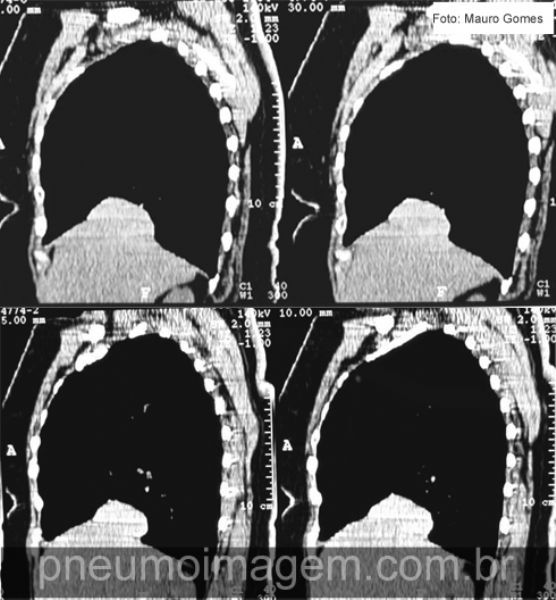

Cortes tomográficos em perfil demonstram a elevação do diafragma. Mesmo com os mecanismos compensatórios ativos, o diafragma afetado gera uma diminuição em torno de 20% na ventilação e perfusão do pulmão correspondente. Quando há sintomas, geralmente a dispneia é o mais evidente. Nesses casos, a plicatura do diafragma pode aliviar os sintomas.

CT slices in lateral view shows the elevation of the diaphragm. Even with the active compensatory mechanisms, the affected diaphragm generates a decrease of around 20% in ventilation and perfusion of the corresponding lung. When there are symptoms, usually dyspnea is the most obvious. In such cases, the plication of the diaphragm can relieve symptoms.

Apesar da diminuição na força inspiratória, muitos pacientes conseguem manter uma ventilação minuto e oxigenação sanguínea dentro da normalidade, mesmo ao esforço, e não apresentam sintomas. Isso acontece devido ao maior recrutamento da musculatura inspiratória acessória, do diafragma não afetado e da musculatura expiratória abdominal.

Despite the decrease in inspiratory force, many patients can maintain a ventilation / minute and blood oxygenation within the normal range, even the effort, and no symptoms. This is due to increased recruitment of accessory inspiratory muscles, increased recruitment of unaffected diaphragm and abdominal expiratory muscles.